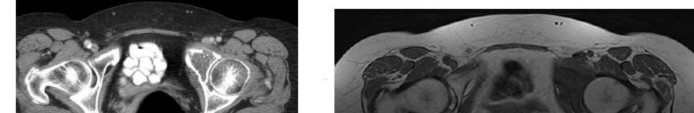

Question 4

A 65-year-old male who underwent a cementless total hip arthroplasty (THA) 15 years ago presents with new-onset thigh pain. Radiographs reveal eccentric positioning of the femoral head within the acetabular shell and large retroacetabular and proximal femoral radiolucencies.

What is the primary biological mediator released by macrophages that directly stimulates osteoclastogenesis and is responsible for the observed bone loss?

Explanation

The radiograph demonstrates particle-induced osteolysis, secondary to polyethylene wear debris. When macrophages phagocytose these particles, they release pro-inflammatory cytokines, most notably TNF-a, IL-1, and IL-6. These cytokines stimulate the RANK/RANKL pathway, activating osteoclasts and leading to significant periprosthetic bone loss. IL-10 and IL-4 are anti-inflammatory cytokines, while IFN-y actually inhibits osteoclastogenesis.